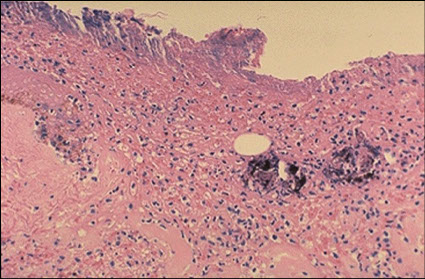

Histology of Point Blank Gun Shot Wound

Low power shows heat damage with focal dark pigmentation

Higher power shows translucent , non-refractile particulate foreign material consistent with gunpowder